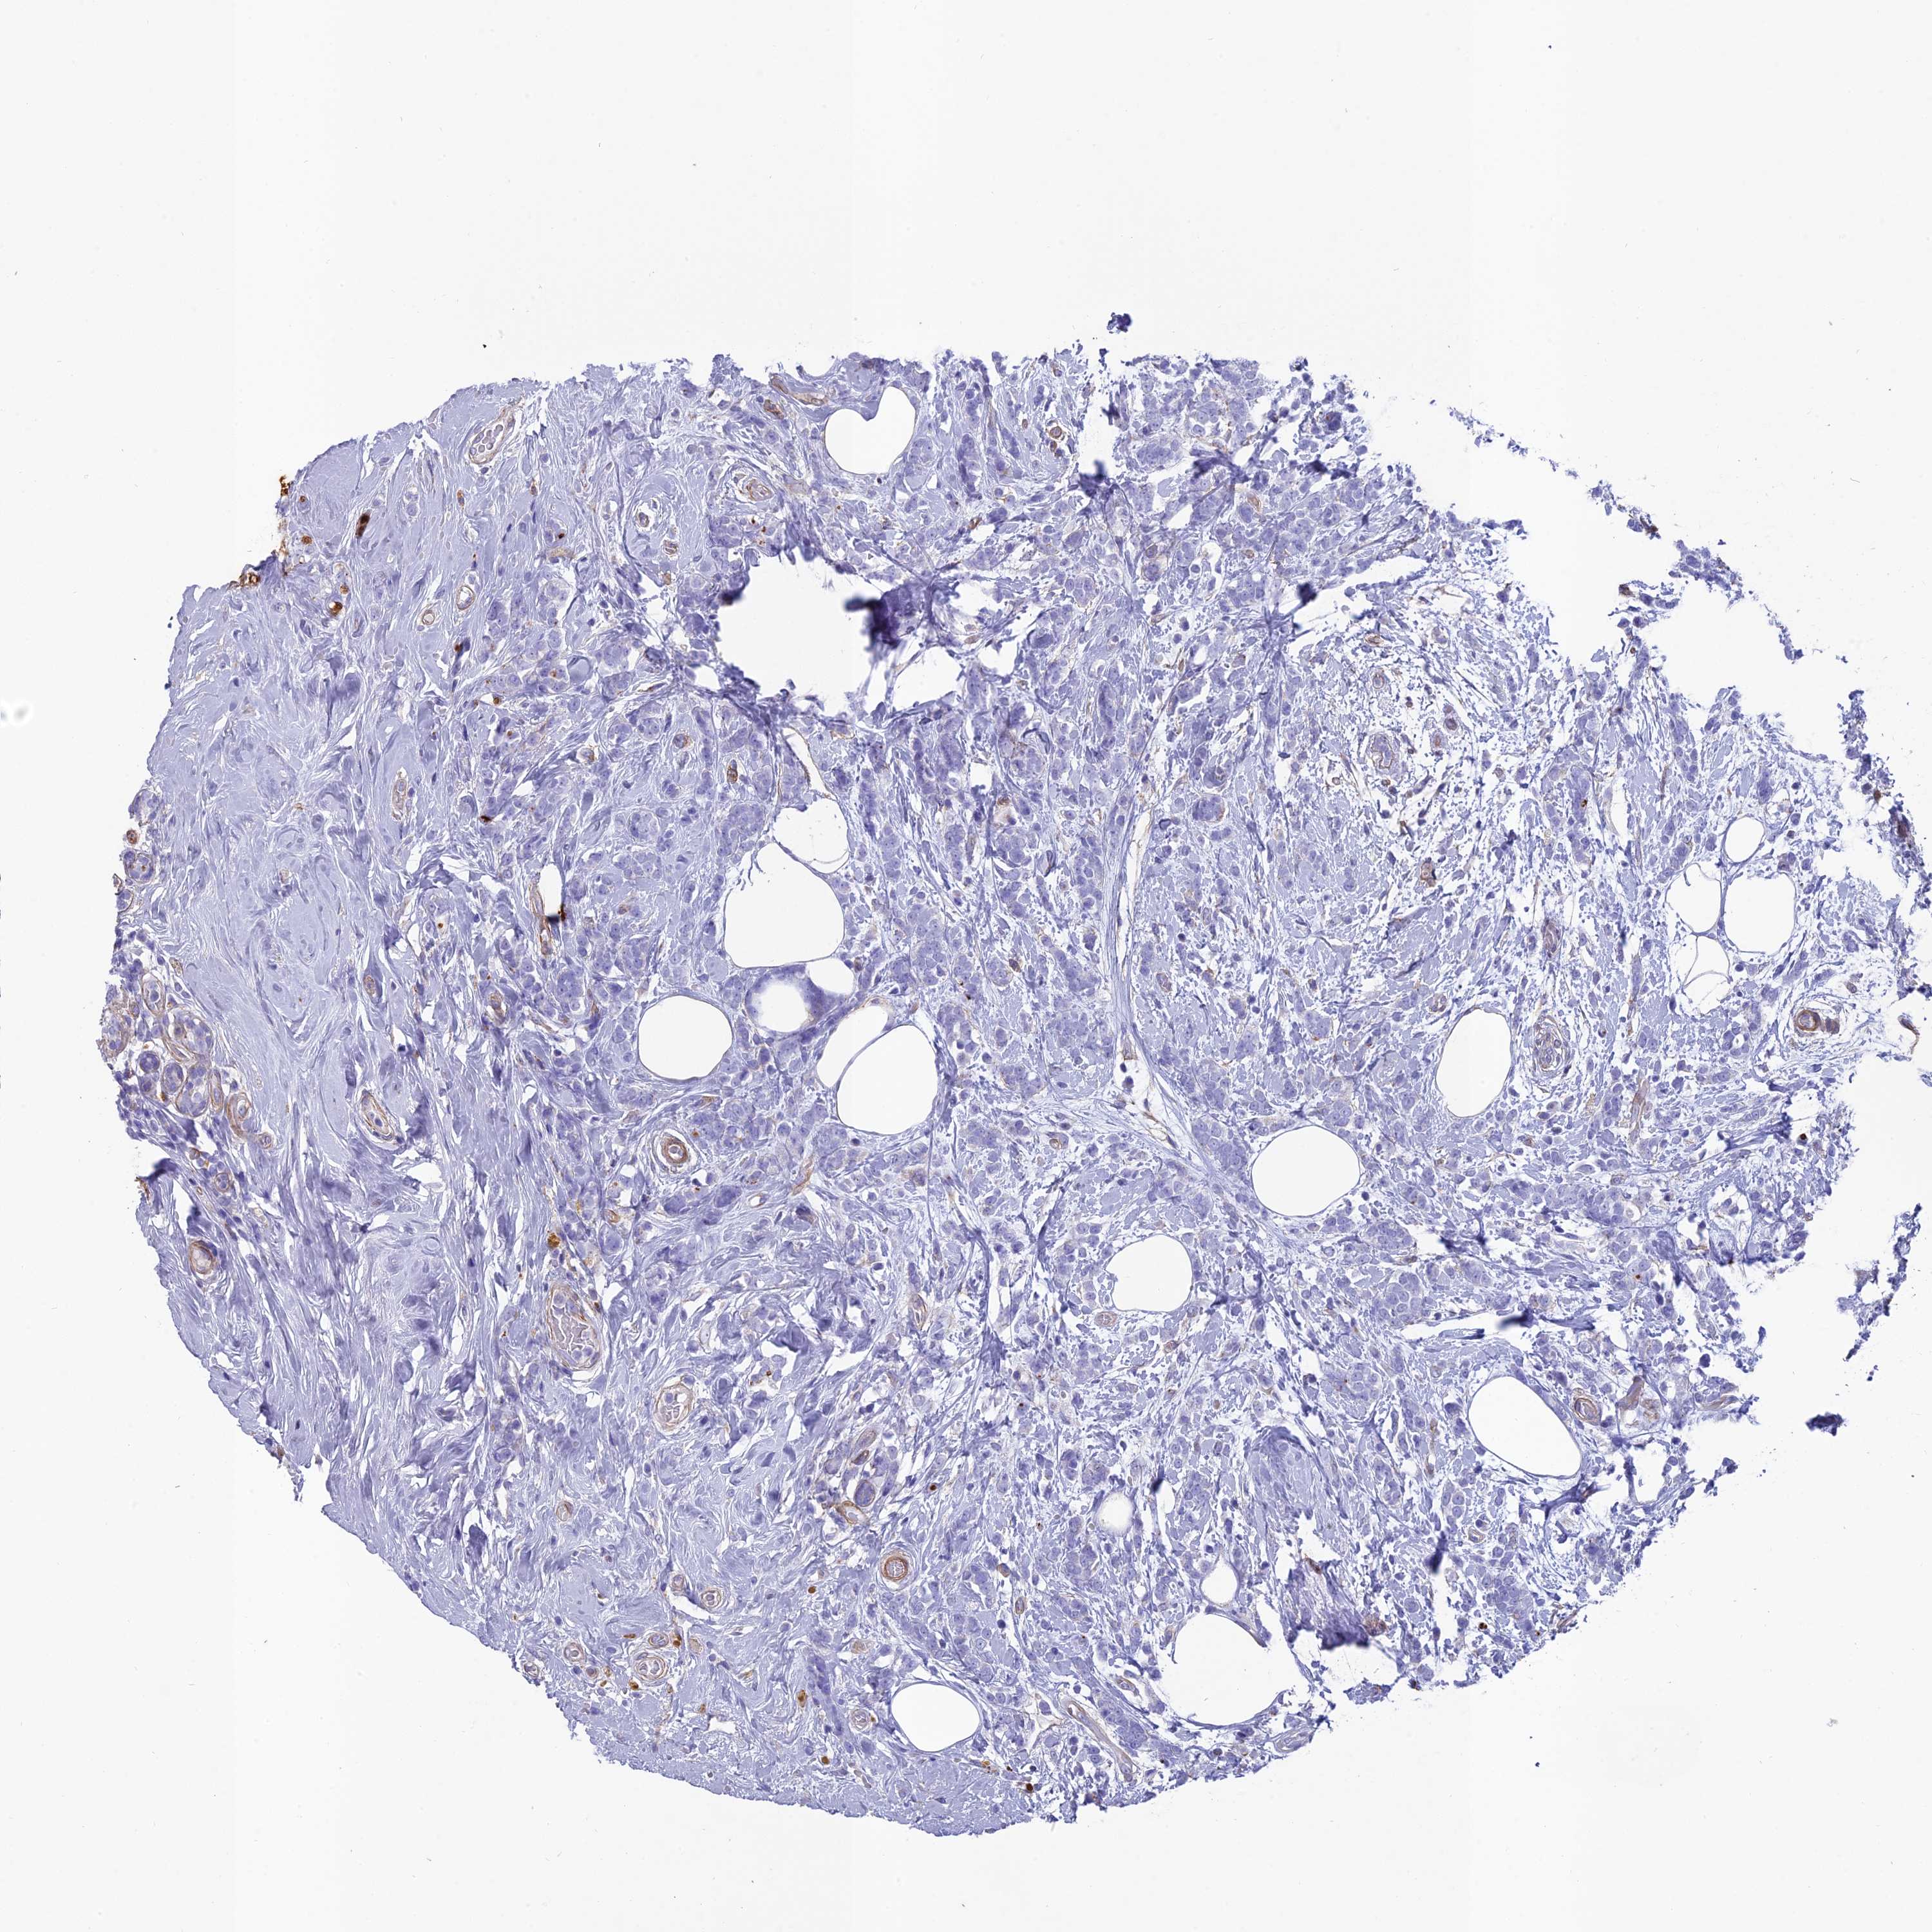

CANCER BREAST CANCER Show tissue menu

Breast cancer

Human cancer